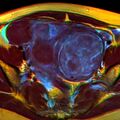

The presence of a uterine fibroid versus an adnexal tumor is made. Fibroids can be mistaken for ovarian neoplasms. An uncommon tumor which may be mistaken for a fibroid is Sarcoma botryoides. It is more common in children and adolescents. Like a fibroid, it can also protrude from the vagina and is distinguished from fibroids.[7] While palpation used in a pelvic examination can typically identify the presence of larger fibroids, gynecologic ultrasonography (ultrasound) has evolved as the standard tool to evaluate the uterus for fibroids. Sonography will depict the fibroids as focal masses with a heterogeneous texture, which usually cause shadowing of the ultrasound beam. The location can be determined and dimensions of the lesion measured. Also, magnetic resonance imaging (MRI) can be used to define the depiction of the size and location of the fibroids within the uterus.[بحاجة لمصدر]